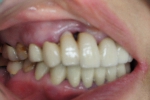

初診時 外見はそれほど歯茎が下がっていないように見えますがかなり深い歯周ポケットが存在していました。